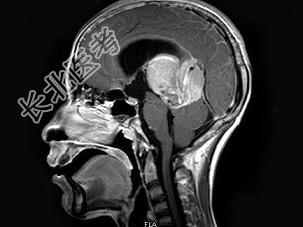

- 单项选择题男,16岁, 头痛数月,MRI平扫及增强扫描如图, 最可能的诊断是 ( )

A、生殖细胞瘤

B、松果体细胞瘤

C、星形细胞瘤

D、室管膜瘤

E、未见异常